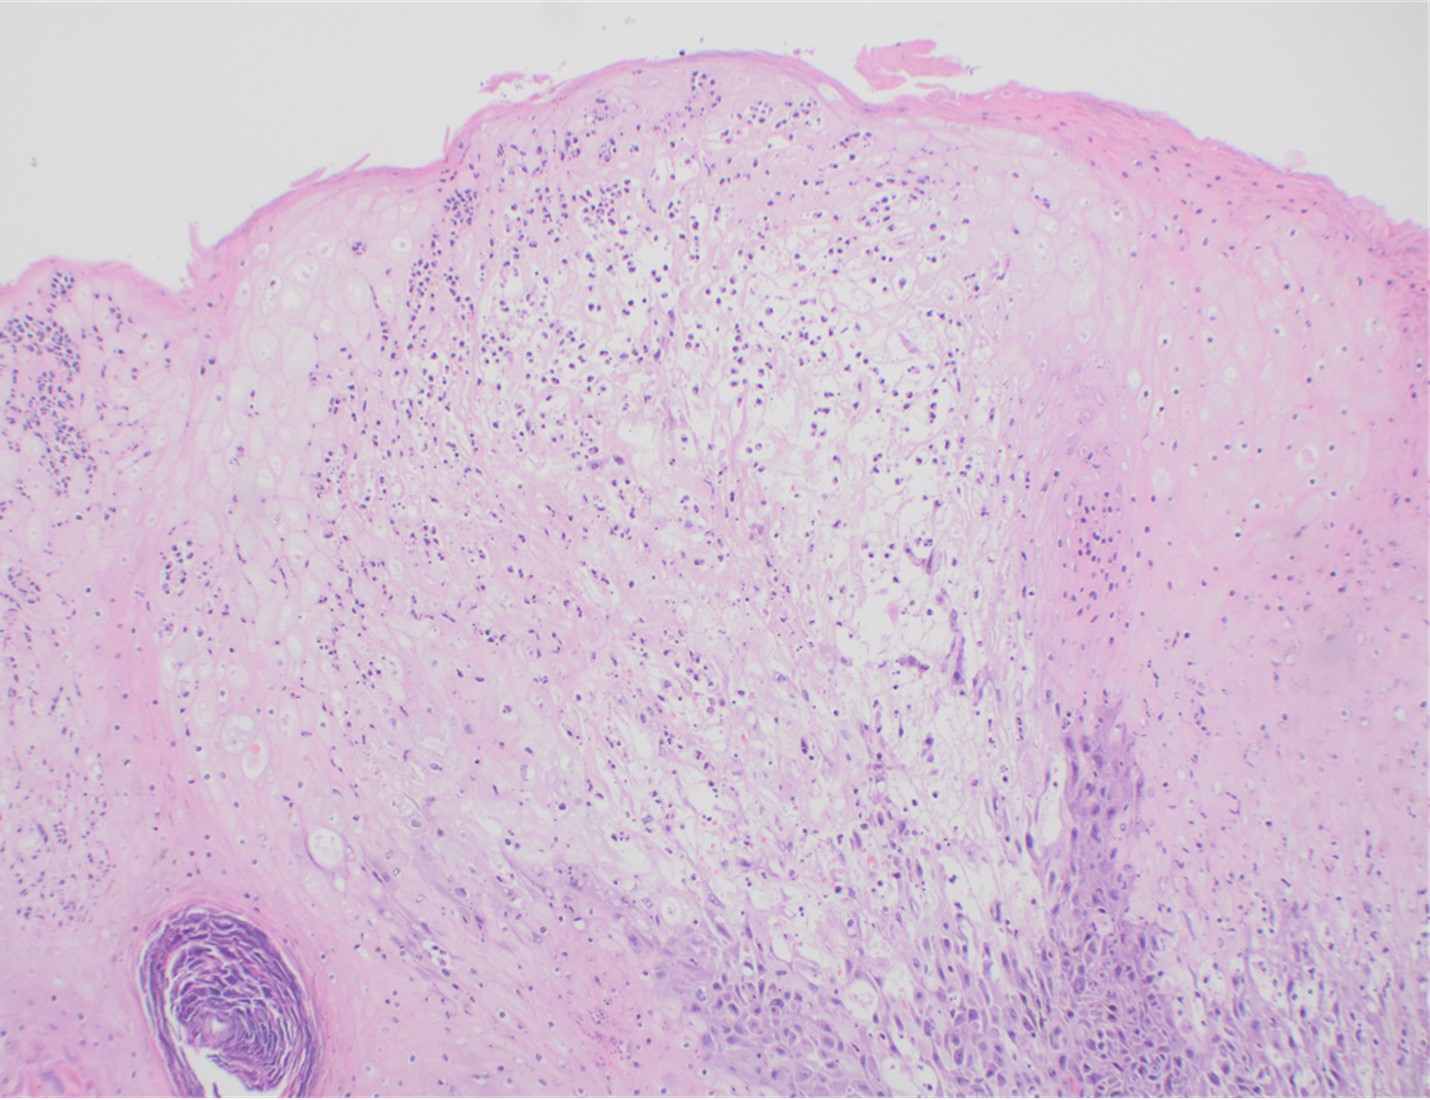

Figure 1. Histopathology of MPOX from a biopsied skin lesion (4x magnification, H&E). Intact epidermis with evidence of ballooning keratinocyte degeneration and infiltration of neutrophils.

Figure 2. Histopathology of Mpox (10x magnification, H&E). Epidermis with a cross-section of follicular infundibulum (hair follicle) is in the bottom left. The keratinocytes to the right demonstrate marked vacuolar change and small eosinophilic bodies can be observed in a background of neutrophils and necrotic keratinocytes.